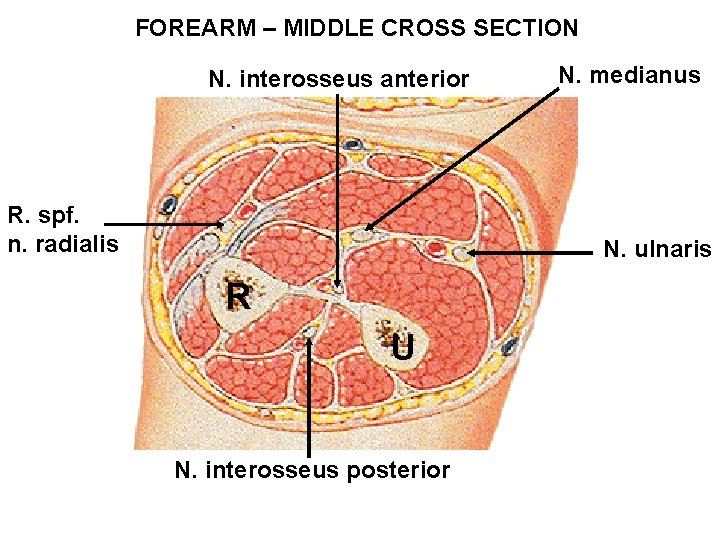

FOREARM – MIDDLE CROSS SECTION N. interosseus anterior R. spf. n. radialis N. medianus N. ulnaris R U N. interosseus posterior